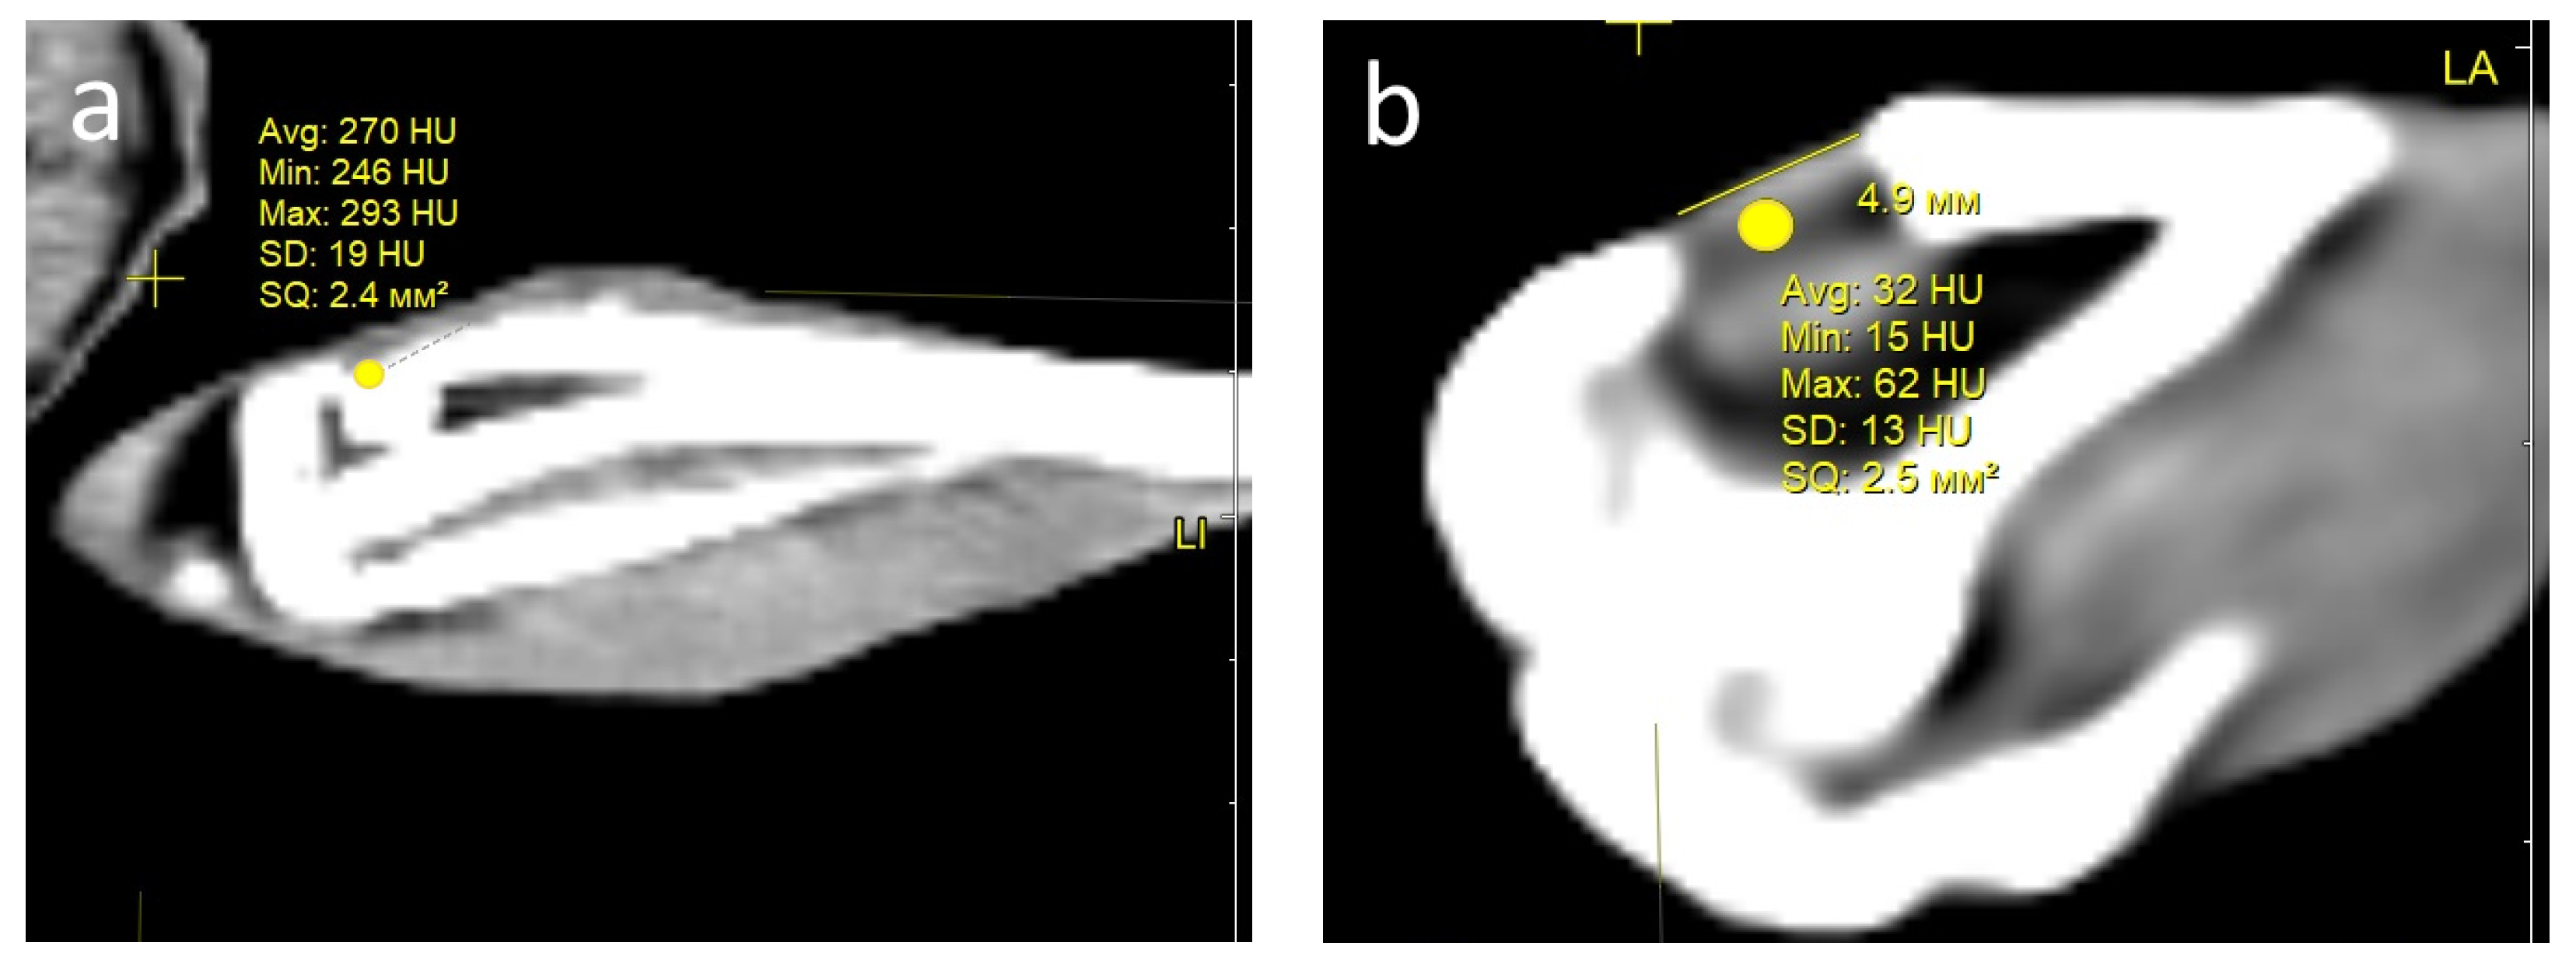

Condition of the defect area and computed tomography (CT) examination. One month after the operation, all rabbits in both groups showed signs of regeneration of the inflicted experimental bone defect in the form of a decrease in its size by 1–2 mm. The size of the defect, determined by CT measurements on the day of surgery, corresponded to the intraoperative measurements. At the CT densitometry assessment of the area after 1 month, the Hounsfield index among all rabbits in the control group (grafted osteoplastic matrix) was 69–271 HU. The average values of the X-ray density of the entire volume of the graft in the animals in this group were 142–229 HU, which indicated the heterogeneous nature of the cavity contents (Figure 8a). The values of this parameter in the experimental group (hybrid polymer) ranged from 15–89 HU. The average values of the X-ray density of the entire volume of the graft in the animals in this group were 31–67 HU (Figure 8b). This very insignificant scattering of values indicated the homogeneity of the graft. In the cortical bone structures adjacent to the defect, the Hounsfield index value was 680–720 HU.

Figure 8.

CT scan—section through the center of the implant in the sagittal direction, observed: at 1 month: (a) control, (b) experiment; at 2 months: (c) control, (d) experiment; at 6 months: (e) control; (f) experiment.

In the animals removed after 2 months, a further decrease in the size of the defect was seen, decreasing to an insignificant size of 1–2 mm. All animals in the control group (grafted osteoplastic matrix) had absolute values of the Hounsfield index from 10–457 HU. The average values of the X-ray density of the entire volume of the graft in the animals in this group were 171–231 HU (Figure 8c). The minimum value in the experimental group (hybrid polymer) was 96 HU, the maximum was 643 H. The average values ranged from 195–453 HU (Figure 8d). The measurements did not reveal any pathological changes in the cortical bone structures adjacent to the defects.

After 6 months, complete recovery of the applied defect was demonstrated in all animals in both groups. However, the Hounsfield index in the control group (grafted osteoplastic matrix) ranged from −60 to 910 HU and continued to demonstrate the heterogeneity of the graft tissue, along with occasional increases above the usual values for shin bone. The average values ranged from 305–577 HU (Figure 8e). The values of the X-ray density of the central part of the graft in the experimental group (hybrid polymer) ranged from 204–814 HU. The average values ranged from 426–615 HU (Figure 8f).

Therefore, the CT data, which includes CT densitometry of the central area of the graft, indicate that the processes of reparative regeneration in the animals in the control and experimental groups differed to some extent. In the control group, at all assessment points, the density of the graft was convincingly heterogeneous, and included areas where minimal X-ray shadow intensity persisted for 6 months. The graft placed into the bone defect in the rabbits in the experimental group demonstrated a stable increase in X-ray density, together with a less significant scatter between the minimum and maximum values of the X-ray shadow intensity.

Consequently, based on the CT image analysis, the authors determined the development of a more uniform structure; therefore, it was concluded that there were more active regenerative processes in the bone defects of the rabbits in the experimental group.